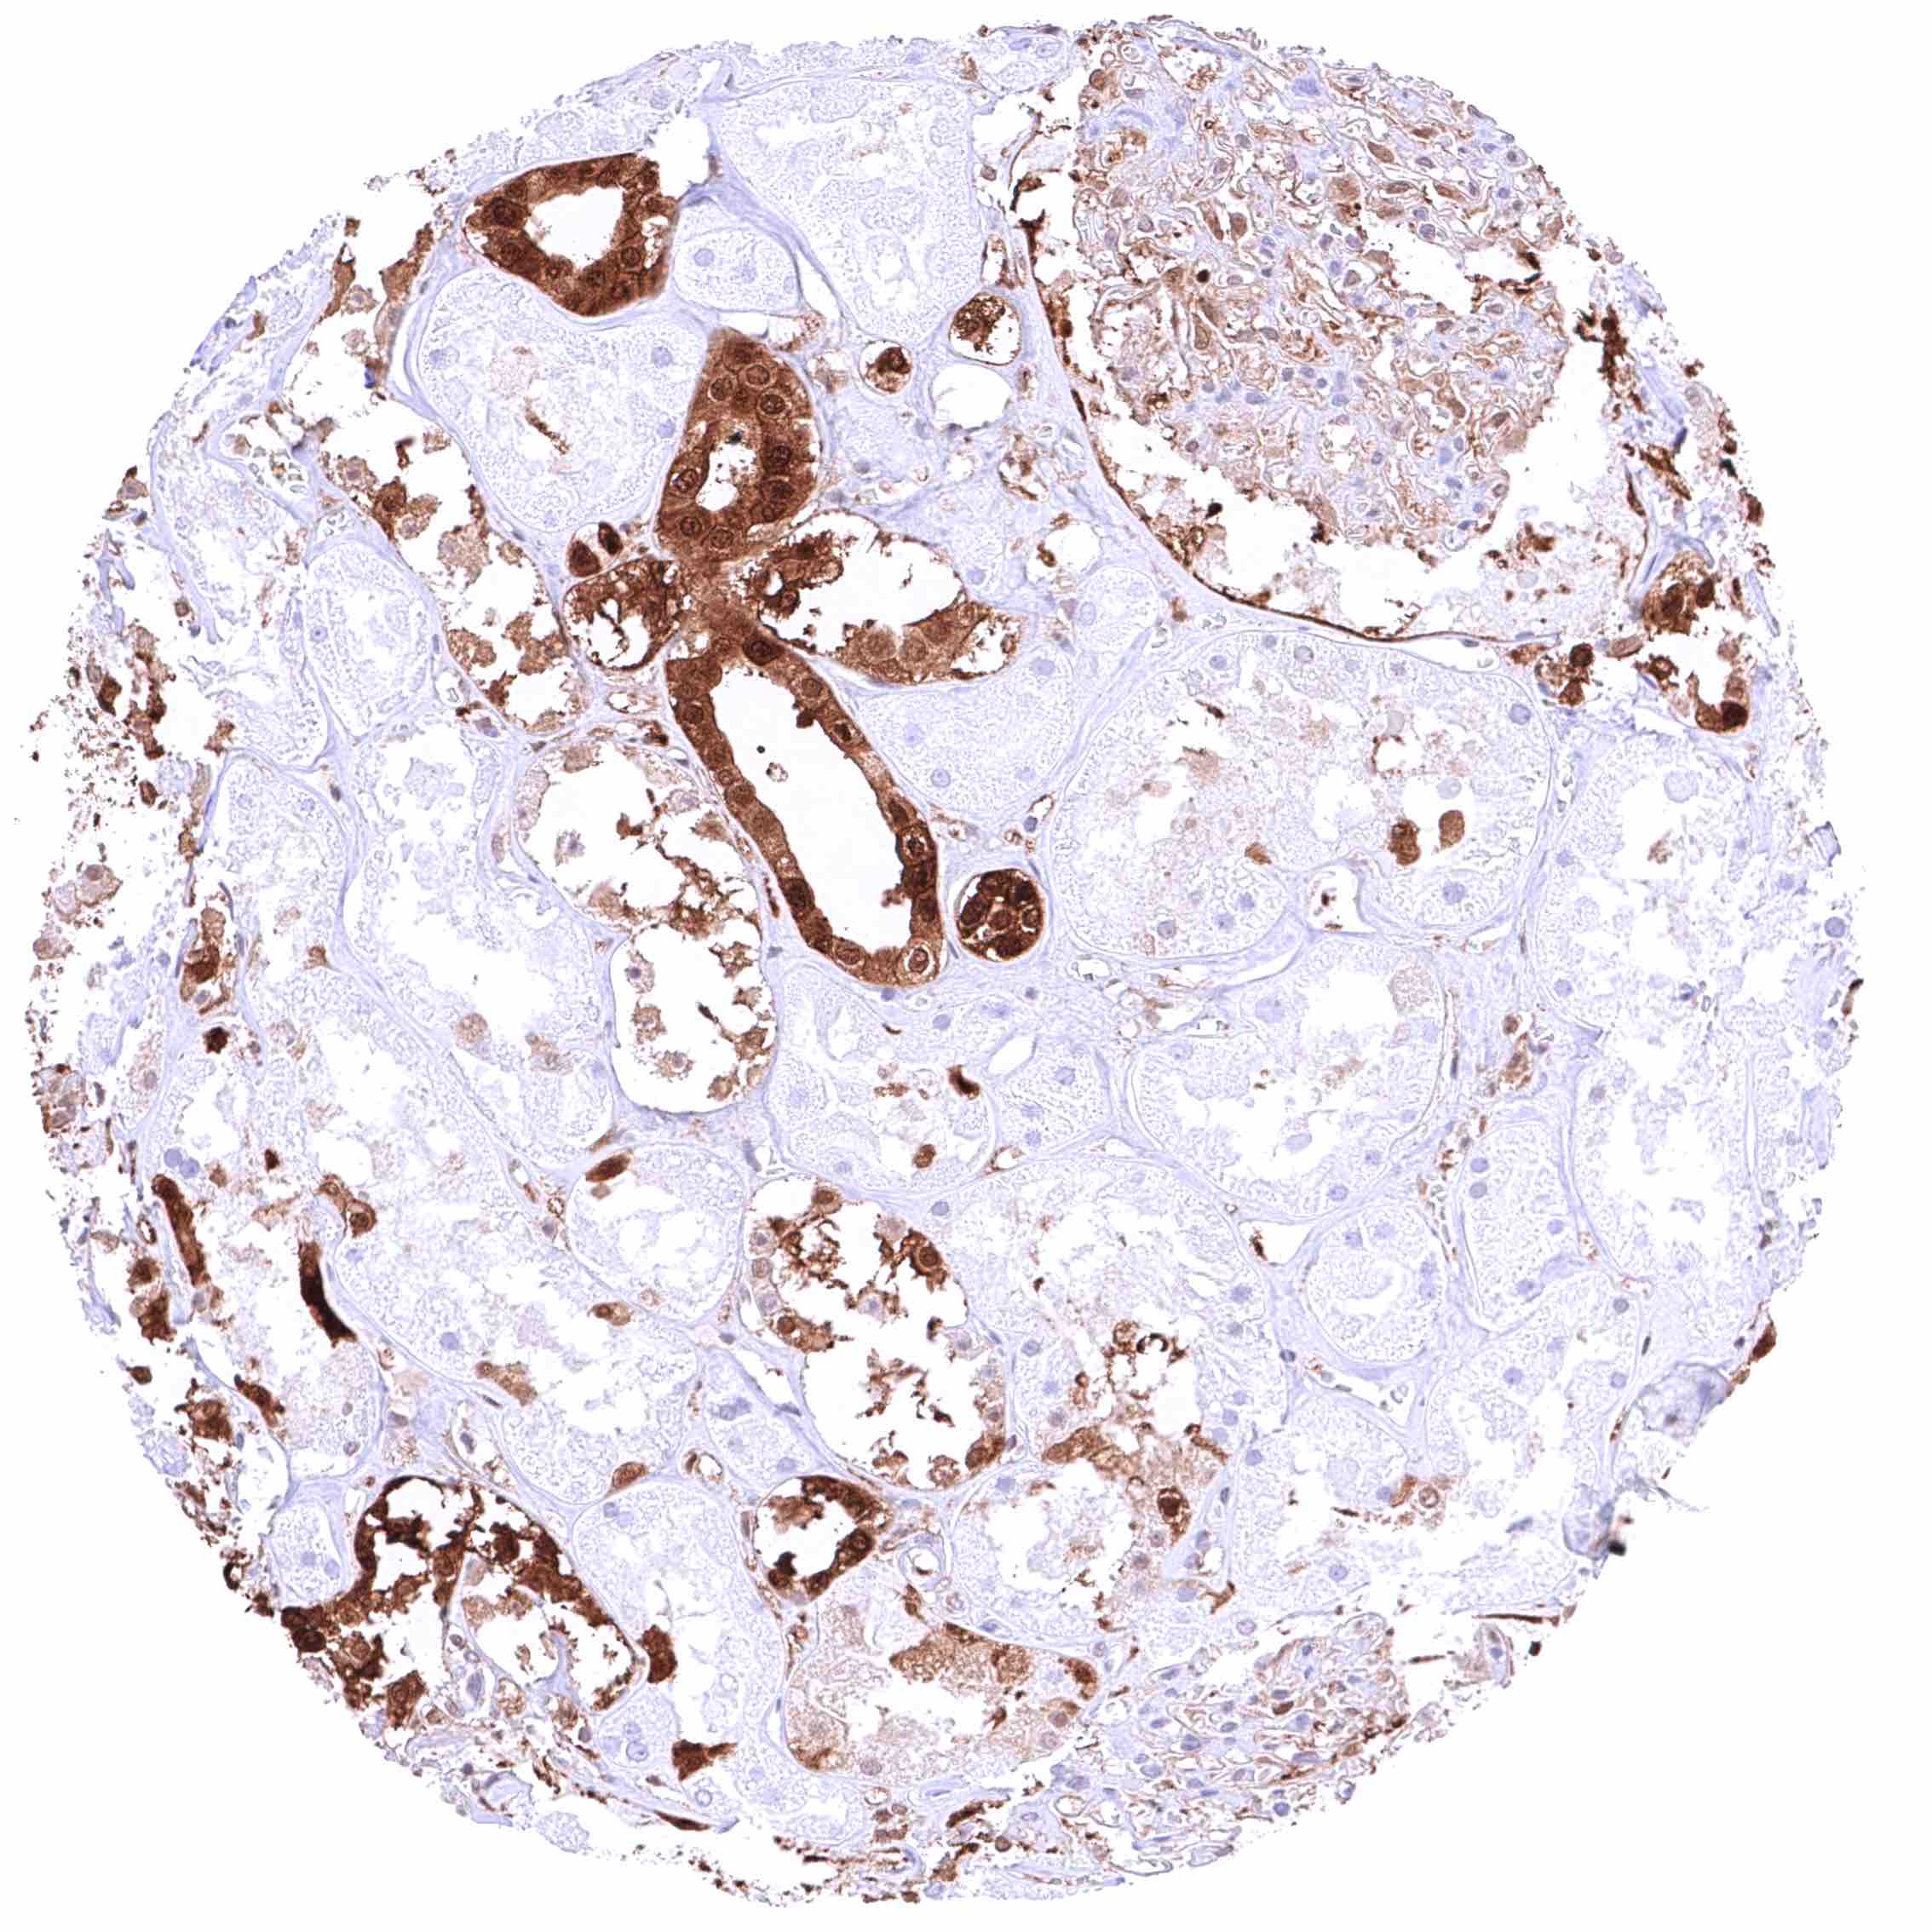

Lung – Moderate, predominantly cytoplasmic positivity of alveolar endothelial cells. Strong, nuclear and cytoplasmic GSTP1 positivity of at least a significant subset of alveolar cells.